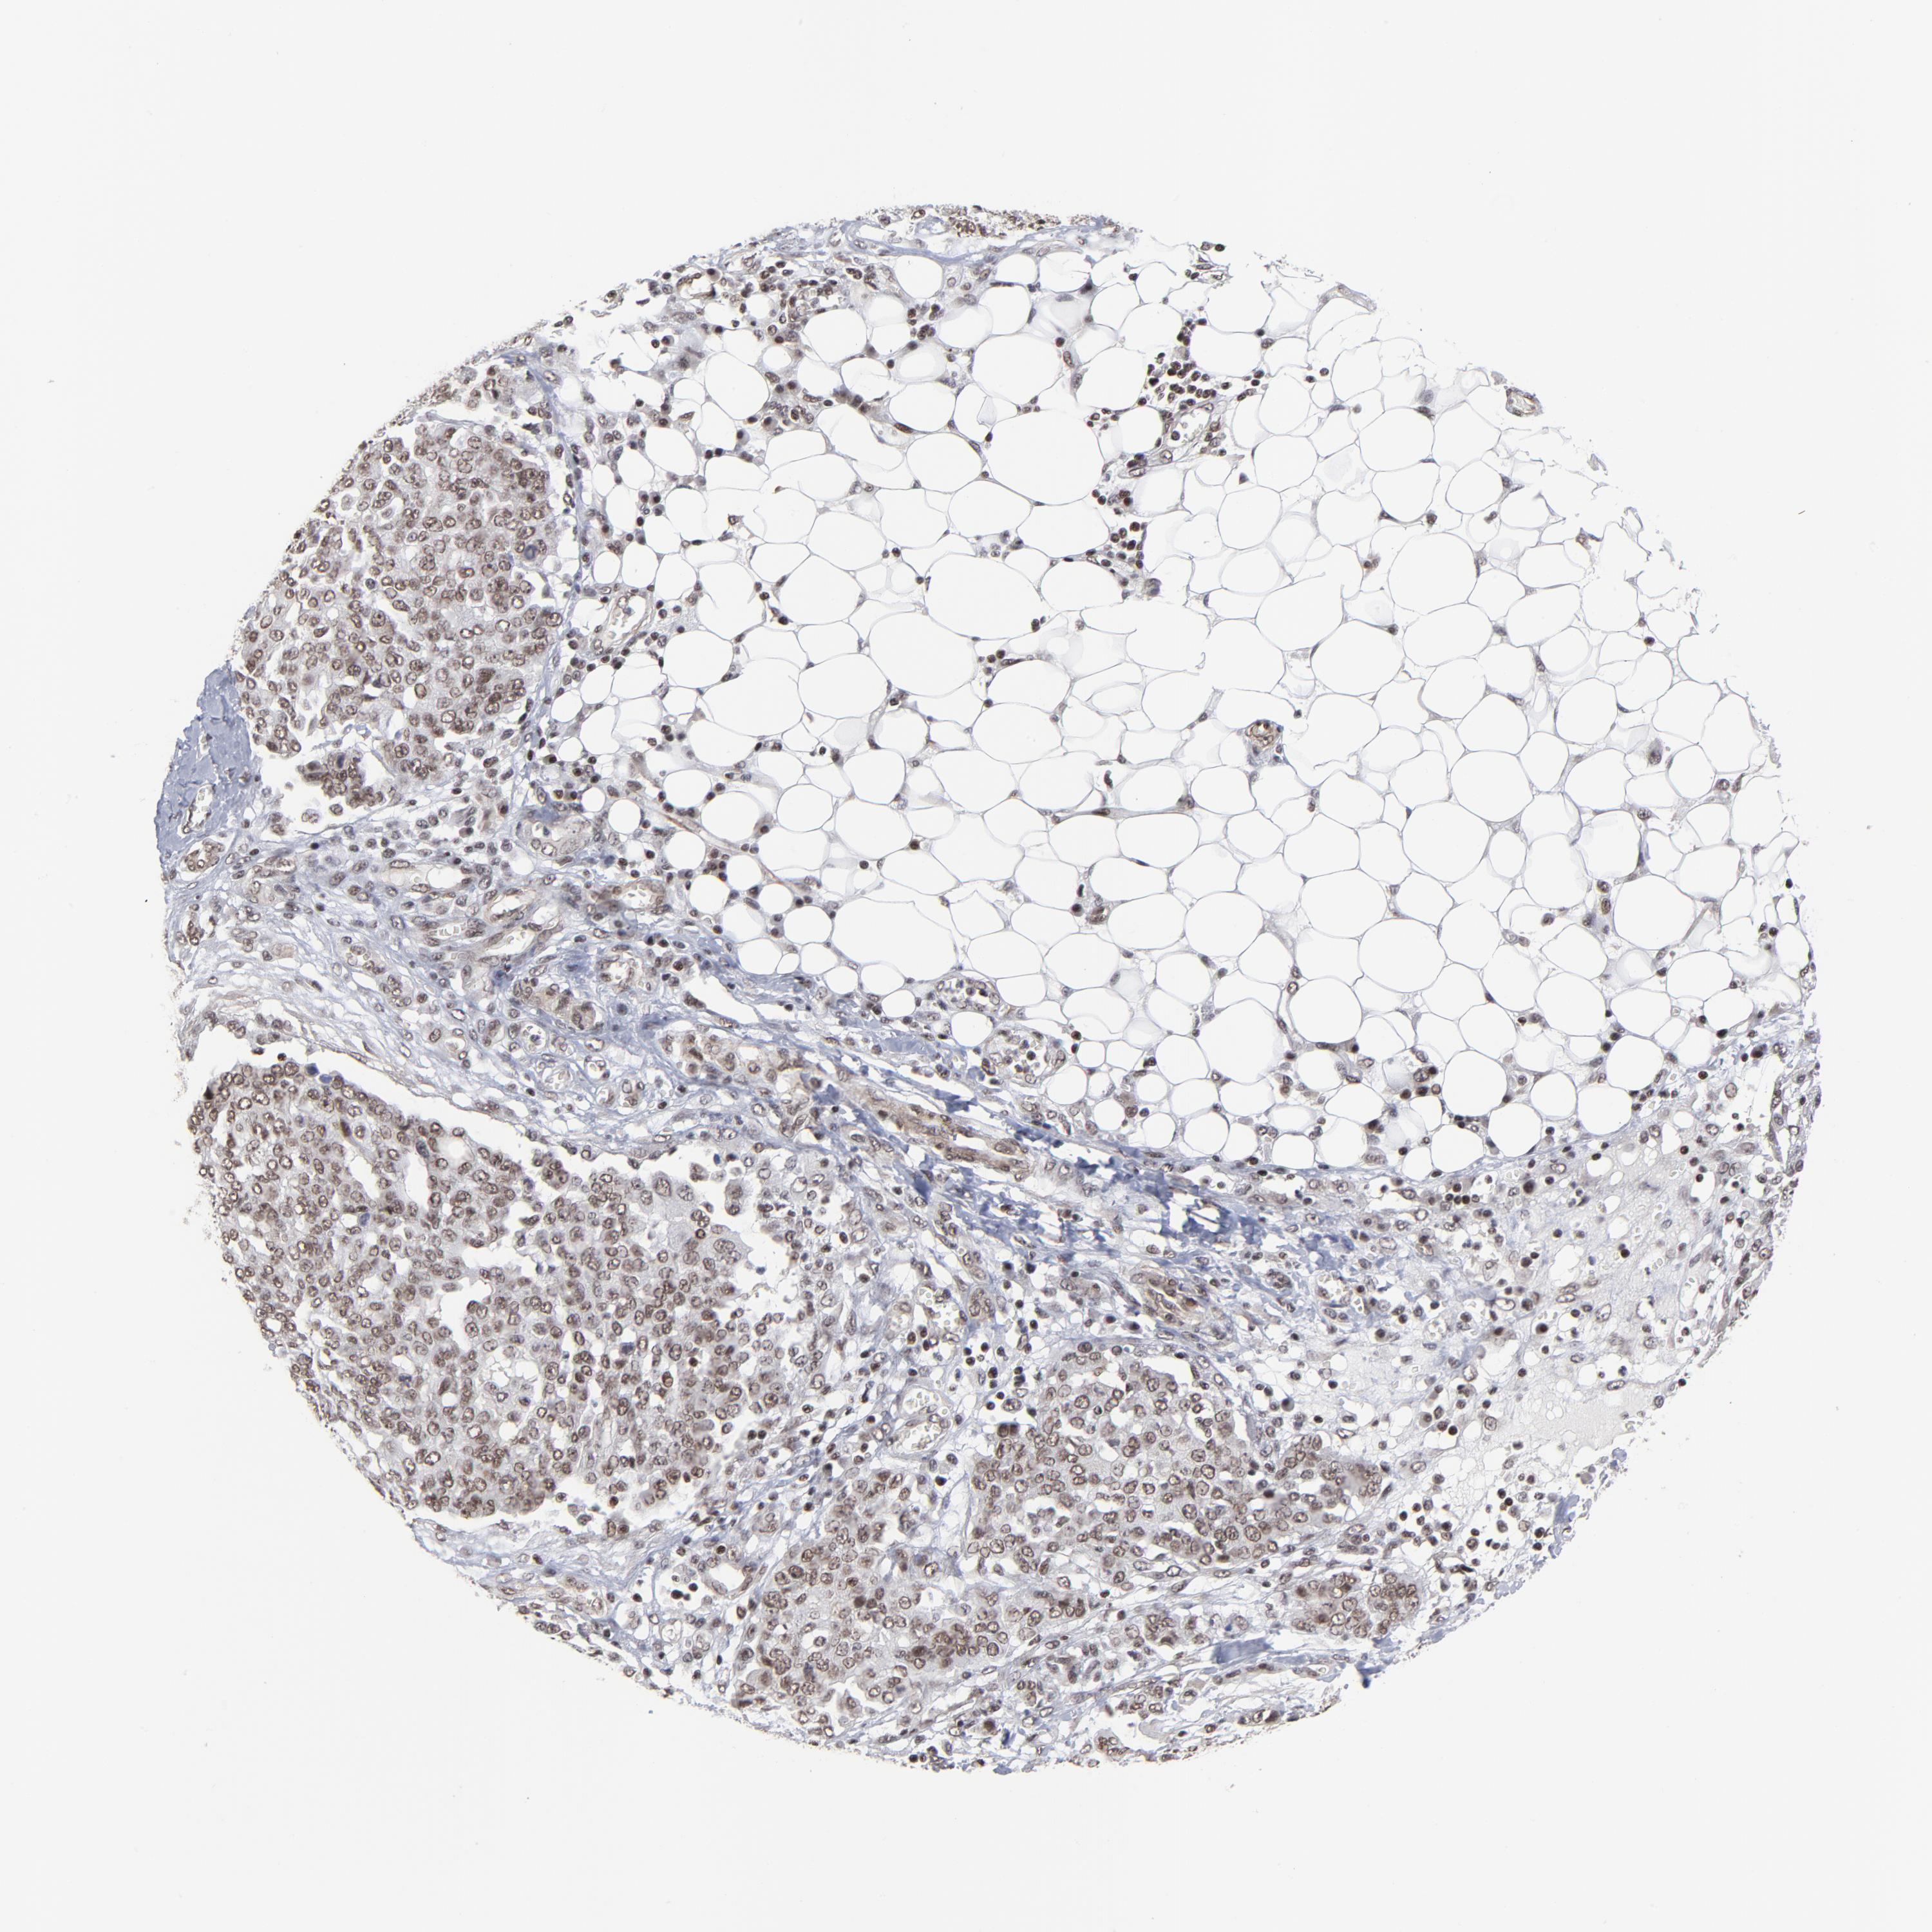

OVARIAN CANCER - Protein expressioni

A mouse-over function shows sample information and annotation data. Click on an image to view it in a full screen mode. Samples can be filtered based on level of antibody staining by selecting one or several of the following categories: high, medium, low and not detected. The assay and annotation is described here.

Note that samples used for immunohistochemistry by the Human Protein Atlas do not correspond to samples in the TCGA dataset.

Antibody stainingi

Antibody staining in the annotated cell types in the current human tissue is reported as not detected, low, medium, or high, based on conventional immunohistochemistry profiling in selected tissues. This score is based on the combination of the staining intensity and fraction of stained cells.

Each image is clickable and will lead to virtual microscopy that enables deeper exploration of all samples and also displays staining intensity scores, fraction scores and subcellular localization as well as patient and tissue information for each sample.

Antibody CAB062550

Cystadenocarcinoma, serous, NOS

Carcinoma, endometroid

Adenocarcinoma, NOS